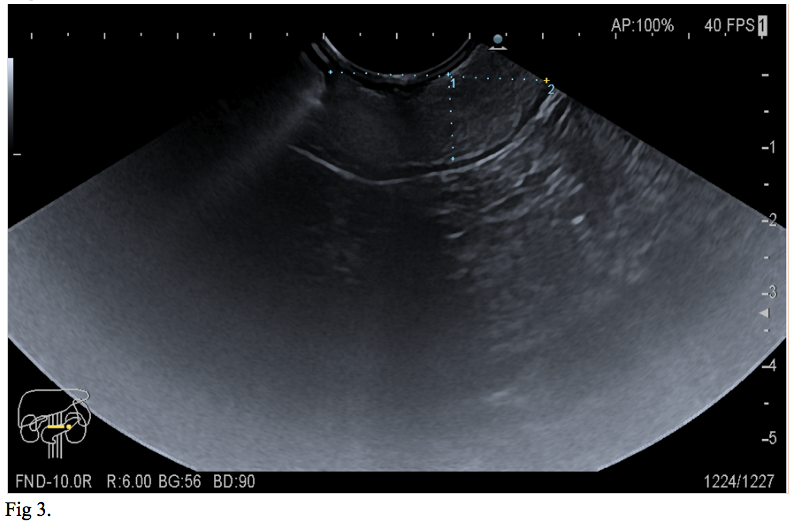

We report the case of a 66-year-old gentleman, known to suffer from high blood pressure, diabetes mellitus type 2, dyslipidemia, cervical and lumbar spondylosis, who presented to the emergency department with asthenia, pallor, melena. On physical examination, the patient was tachycardic with a heart rate of 120, and had a blood pressure of 100/60. He was pale but conscious and orientated. Cardiovascular and respiratory examinations were normal. His abdomen was soft, non-distended, bowel sounds were present and no palpable masses were felt. His laboratory investigations showed a mild normochromic, normocytic anaemia, low haematocrit, hyperglycemia, hypercholesterolemia. The patient was initially resuscitated and stabilized with intravenous fluids and proton pump inhibitors were initiated (iv 80 mg bolus and continuous infusion 8 mg/h). A naso-gastric tube was inserted which produced 300 ml of fresh blood. The patient underwent an urgent upper GI endoscopy which revealed an antral submucosal tumour with an ulcer over the mass. No active bleeding was seen during the procedure. A CT scan of the abdomen and pelvis highlighted a 30/20/18 mm oval shaped soft tissue lesion of fat density arising from the posterior wall of the stomach, with no associated lymphadenopathy. The liver, spleen, and pancreas all appeared normal (Fig 1,2). EUS has been performed and revealed a 30/18 mm intensely hyperechoic lesion continuous with the submucosal layer of the GI tract wall. The lesion was also soft on elastography, and as all the features were suggestive of a benign lesion, tissue sampling was not performed at that stage (Fig 3,4). The patient’s case was discussed at the Tumor Board meeting. The joint decision was to proceed with an exploratory laparoscopy and resect the benign mass. Histopathological examination confirmed the diagnosis of lipoma (Fig 5,6).

Regarding our case, based on the endoscopic appearance and location of the SELs, gastrointestinal stromal tumor (GIST), a neoplastic lesion with malignant potential was the most likely diagnosis. Differential diagnosis included surely benign lesions such as a lipoma, leiomyoma or schwannoma. The diagnosis of lipoma was suspected on abdominal CT scan and was confirmed by EUS. The joint decision to proceed with an exploratory laparoscopy and resect the benign mass was made based on the latest recommendation of the American Society for Gastrointestinal Endoscopy (ASGE). The suggestion of ASGE was that symptomatic GI lipoma should be resected or followed up.

Initial management of SELs centers on proper diagnosis and determination of any malignant potential of the lesion. EUS is the most accurate imaging test for evaluation of SELs of the GI tract. Lipoma is a well-defined hyperechoic lesion arising from the submucosal layer and does not require follow up or therapy unless is symptomatic.